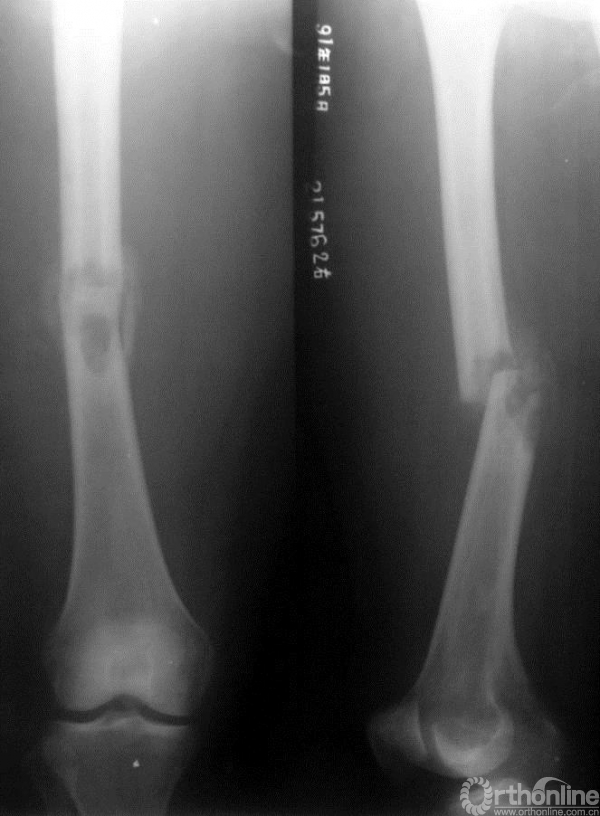

图15-4 第一次术后5个月X线平片正侧位,显示原骨折处发生内固定断裂

二次术前考虑一次手术时内固定方式仅为普通的髓内针,强度不足,且填充的骨水泥影响骨折愈合;此次未见明确局部复发,因此行髓内针及骨水泥取出、取髂骨植骨、钢板内固定术